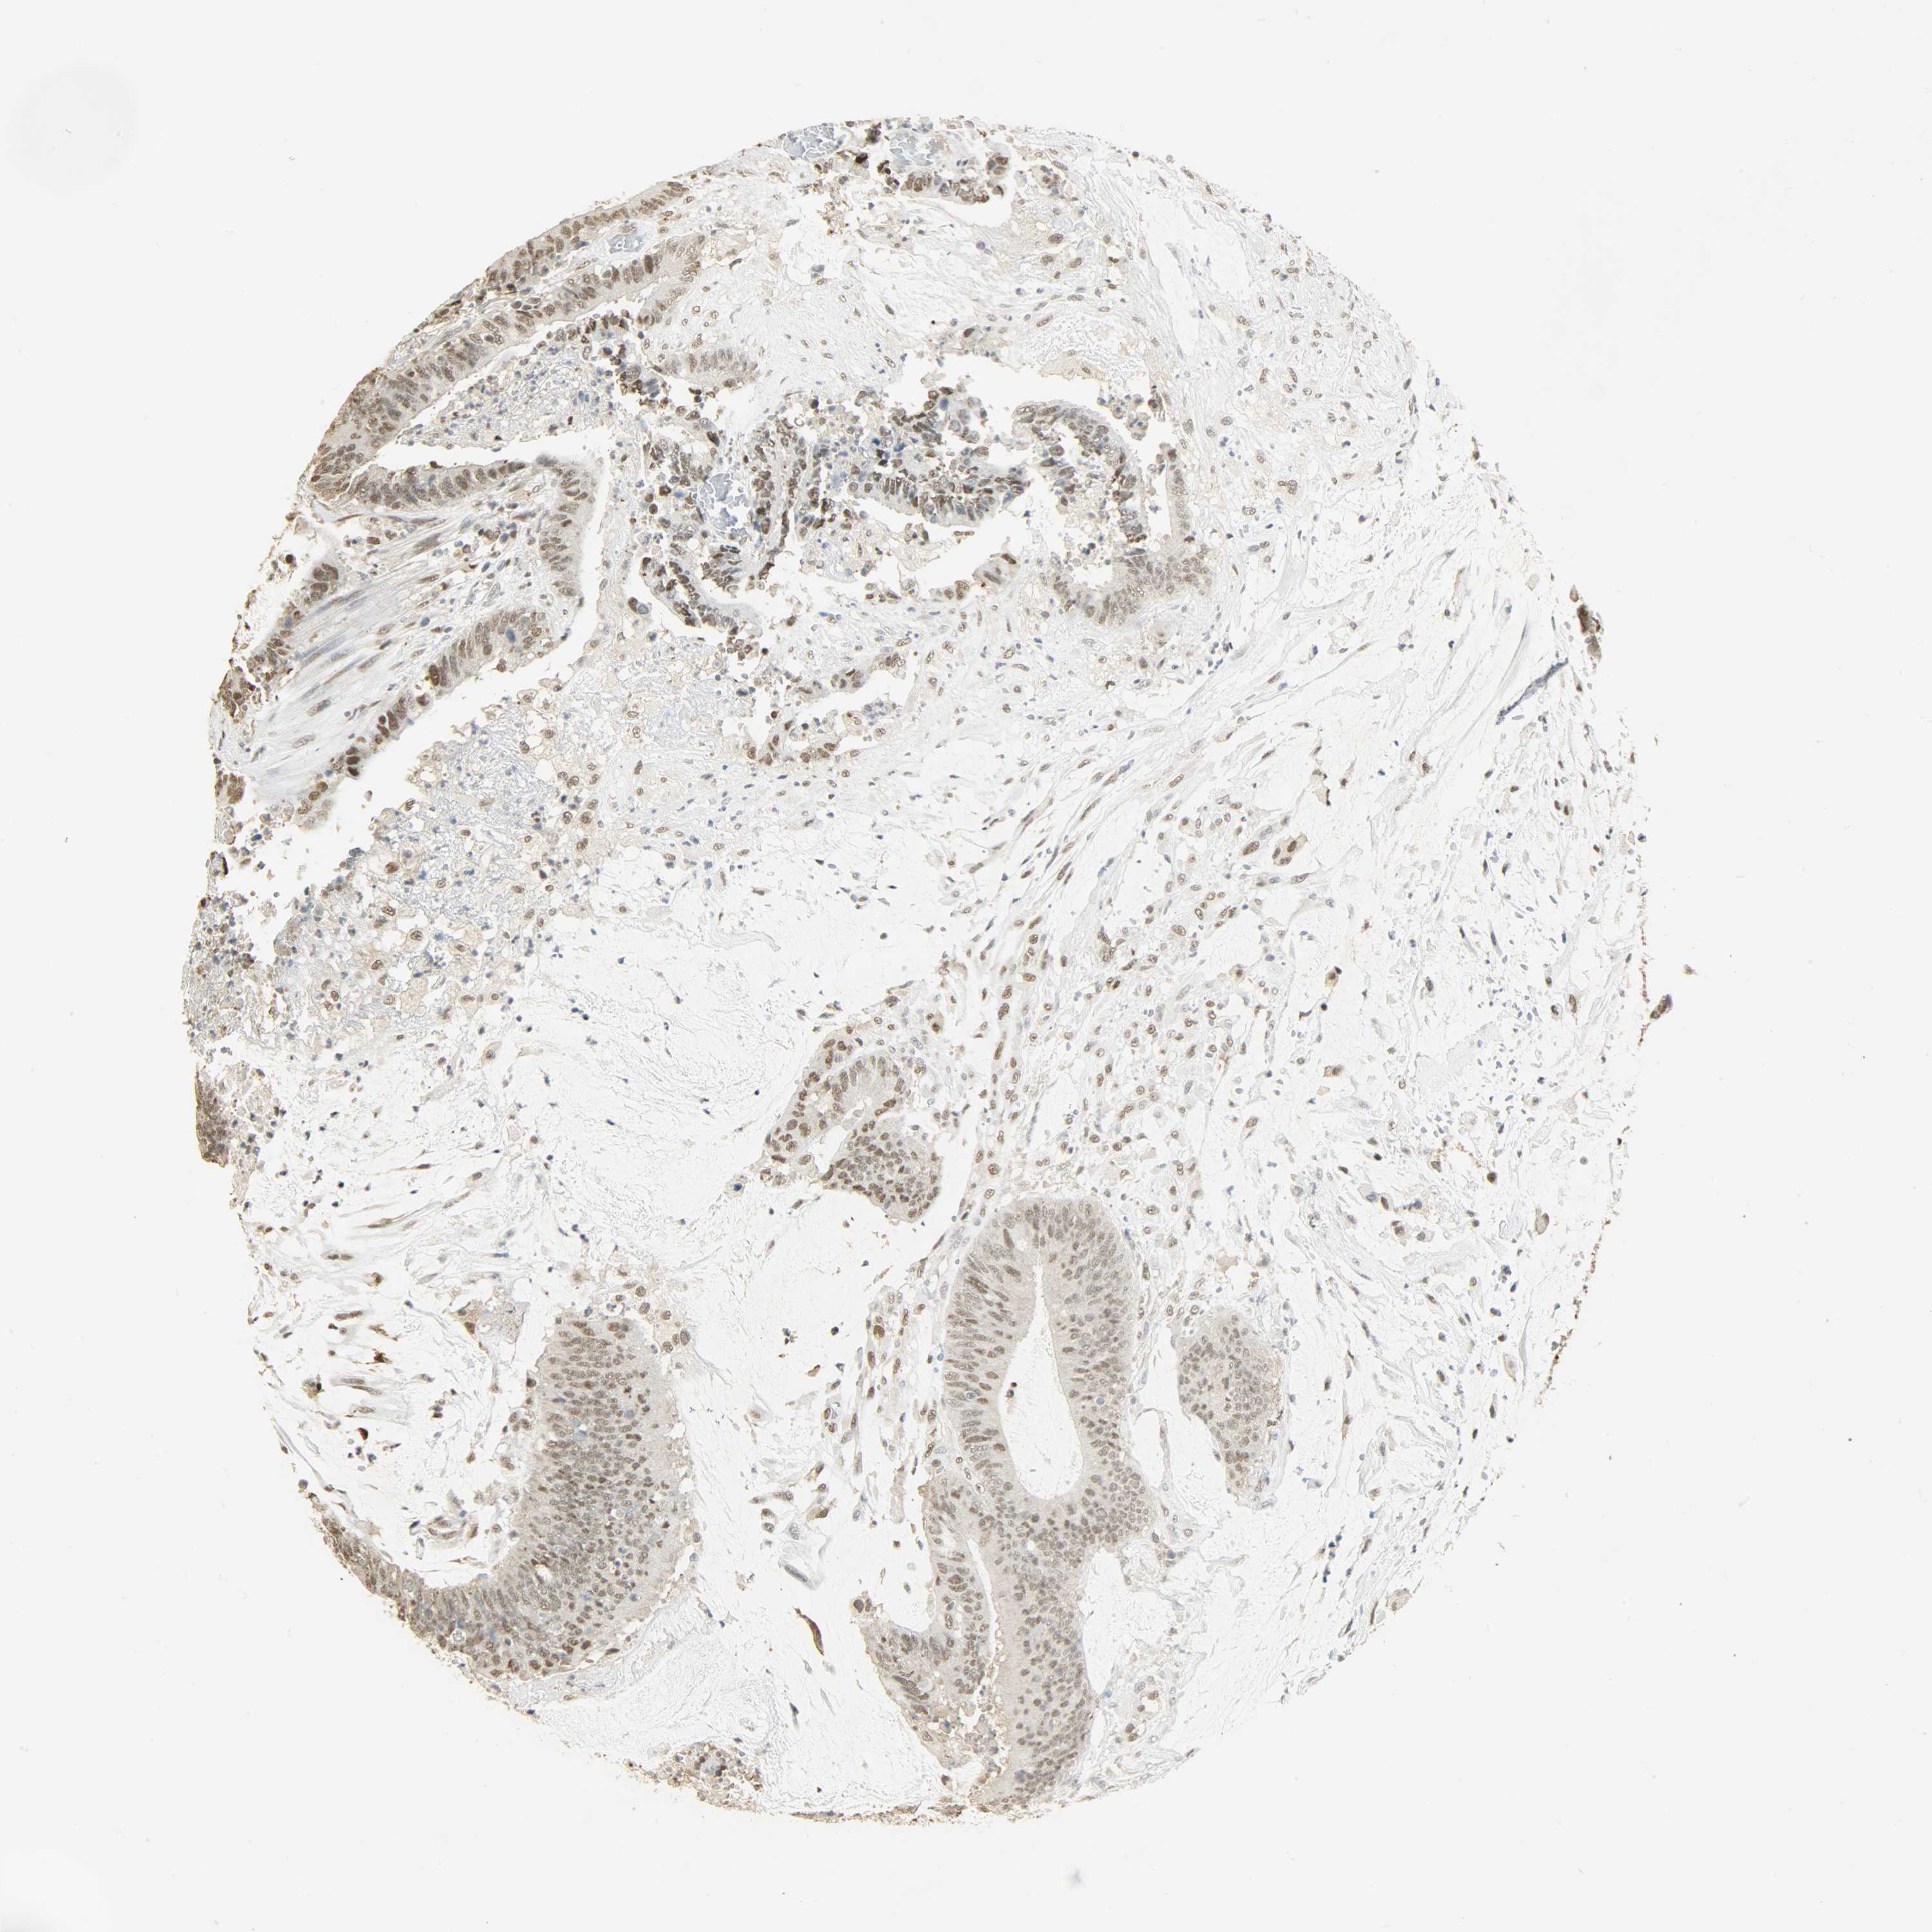

Colorectal cancer

Human cancer

Colon adenocarcinoma